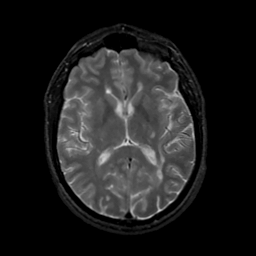

MR Study #13, May 19, 1991 -- Slice #27